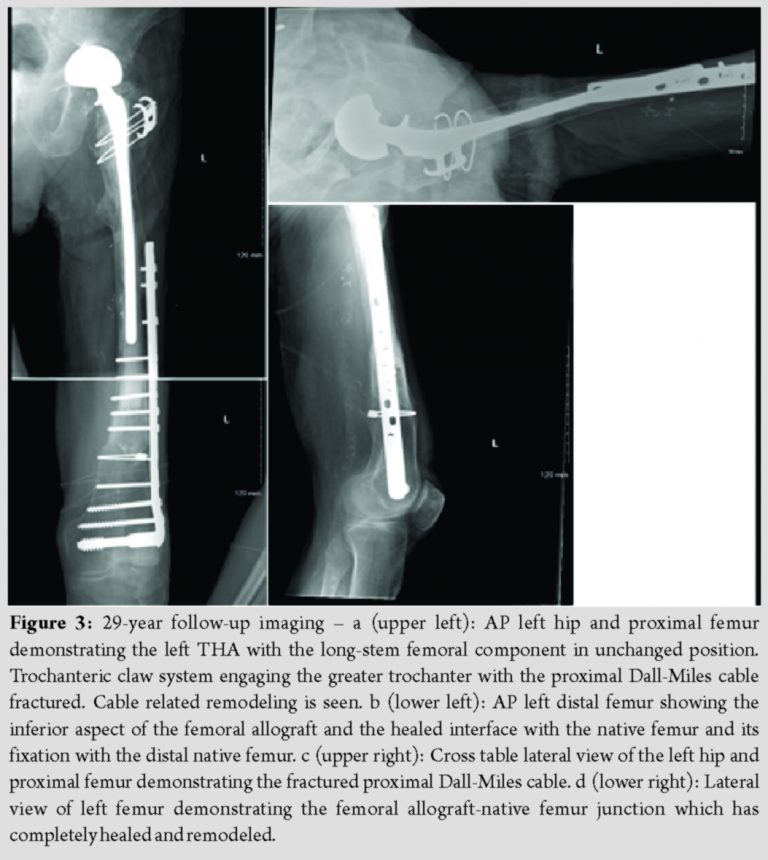

To minimize dislocation risk, a bipolar head was then attached to the femoral trunnion. The composite femoral reconstruction was then reduced and fit nicely into the acetabular component. The native greater trochanter was attached to the proximal allograft with a trochanteric claw device and two Dall-Miles cables, one of which was passed through the allograft lesser trochanter and one below it. The capsule was then repaired, and wound closure was performed in standard fashion. The patient was extubated and transferred to the inpatient floor where he followed an uneventful post-operative course. He was discharged to home after 2 weeks of inpatient rehabilitation with 60 pounds weight-bearing for 3 months. He then progressed to weight-bearing as tolerated with crutches and subsequently with a cane. He returned to full pre-operative activity levels within the 1st year. The allograft native femur junction healed robustly with a significant callus formation. The greater trochanter osteotomy, however, resulted in painless non-union. In the decade following his reconstruction, the patient’s PD progressed throughout his pelvis and left hip and began to invade the medial aspect of the allograft. He was followed by his endocrinologist who treated him with bisphosphonate therapy. He noted minimal left hip or thigh pain after the first 3 months following his reconstruction. He lived at home with his wife, walked with a cane, and cared for his home and yard (Fig. 1a and b). In the 2nd decade following his reconstruction, the invading PD on the medial aspect of the allograft remained stable. There were no signs of loosening of the cement mantle of the long-stem bipolar prosthesis, though the prosthesis itself had migrated somewhat medially. The cables remained intact but had started to cut medially into the allograft. His right hip progressed to moderate arthritis, though he did not complain of pain. He did not have any left hip pain or stiffness (Fig. 2a and b). Twenty years after his reconstruction, the patient was 90 years old and experienced only mild left hip pain worsened with activity. The patient remained relatively active and was able to ambulate independently. The greater trochanter osteotomy remained in stable, asymptomatic non-union. At the post-operative year 21 mark, the left acetabulum began demonstrating radiographic signs of wear with thinning superiorly. At the 24-year mark, the bipolar component began to exhibit signs of early acetabular protrusio. At the 28-year mark, the bipolar component developed further acetabular protrusio. During the entire period of follow-up, the cement mantle within the allograft around the femoral stem remained intact without signs of loosening or subsidence (Fig. 3a, b, c, d). At 28 years post-operative, the patient sustained a right hemispheric stroke that resulted in the left lower extremity weakness. He then transitioned to an assisted living facility. He is presently 99 years old and is mobile with a wheel chair without any left hip or thigh discomfort.